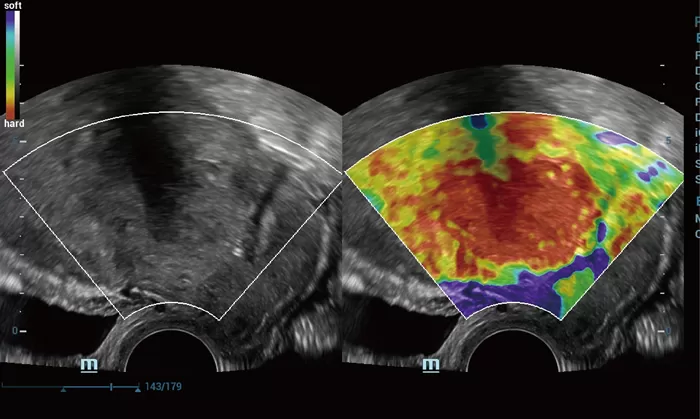

Στη διάθεση σας θα βρίσκονται καταρτισμένοι συνεργάτες μας οι οποίοι θα αναλάβουν να σας παρουσιάσουν τις δυνατότητες του Premium υπερηχογράφου Resona που αποτελεί μια πραγματικά επαναστατική πλατφόρμα, με δεκαπλάσια ταχύτητα σάρωσης χάρις στη μοναδική τεχνολογία zone sonography technology ZST+ που διαθέτει.

Η σειρά Resona ξεχωρίζει όχι μόνο για την κορυφαία απεικονιστική της τεχνολογία αλλά και για τα ευέλικτα εργαλεία ανάλυσης, προσφέροντας ποιότητα απεικόνισης υψηλού επιπέδου και αυξημένη διαγνωστική ακρίβεια.

Οι καινοτόμες τεχνολογίες:

- New iLive with Hyaline

- Smart Face

- Dynamic Focusing

- HD Scope

καθιστούν τη σειρά Resona μια από τις πιο ισχυρές διαγνωστικές πλατφόρμες που υπάρχουν σήμερα στην υπηρεσία της Ιατρικής.